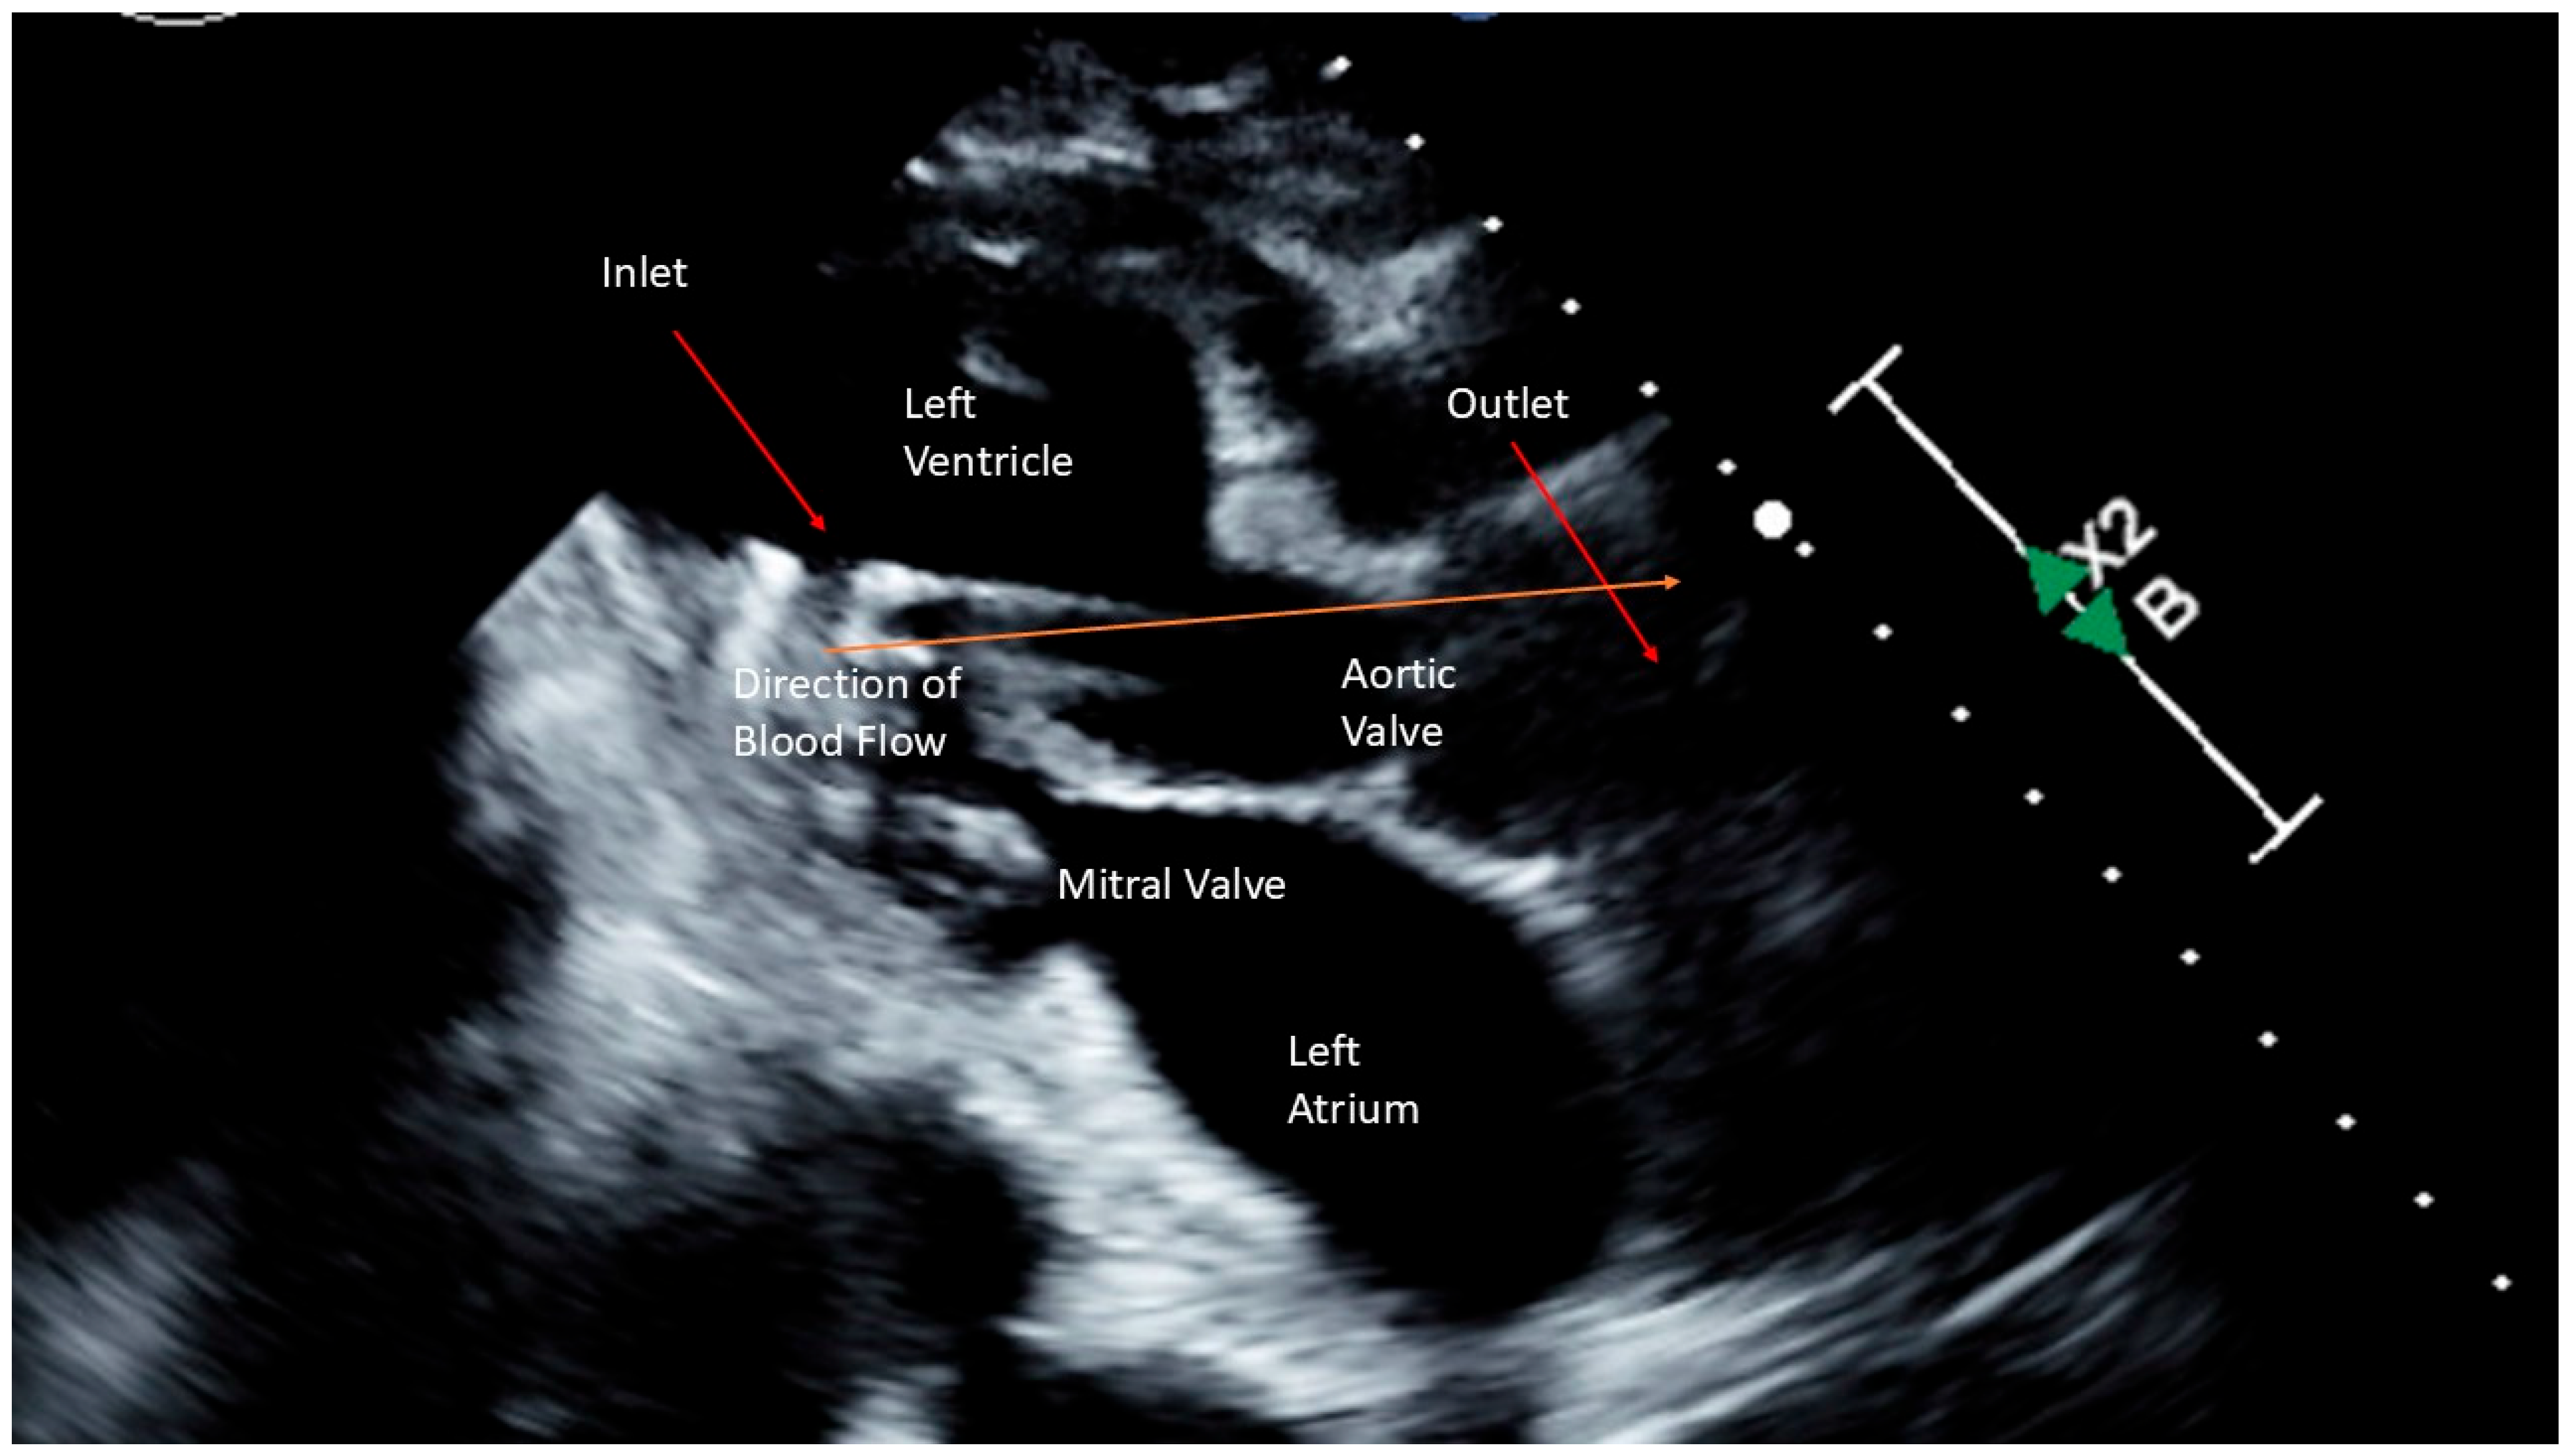

2.1. Case 1